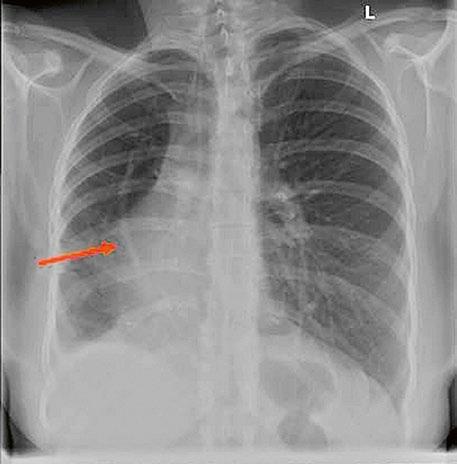

Supravalvární pulmonální stenóza a stenózy větví plicnice bývají součástí komplexních VSV (např. Fallotovy tetralogie) nebo syndromů (Williamsův syndrom, syndrom Noonanové, syndrom vrozené rubeoly, Alagillův syndrom aj.) (Obr. 45.39). Získané stenózy větví plicnice, ale i úplný uzávěr větve plicnice můžeme vidět po spojkových operacích podle BlalockaTaussigové (Obr. 45.40, Obr. 45.41). Pro zobrazení supravalvárních a periferních stenóz plicnice je optimální CT angiografie (Obr. 45.40, Obr. 45.41, Obr. 45.42, Obr. 45.43).

Obr. 45.40 CT angiografie, 8mm stenóza a deformace levé větve plicnice (šipka) po spojkové operaci podle BlalockaTaussigové v dětství LPA – levá větev plicnice, PA – kmen plicnice, RPA – pravá větev plicnice

Obr. 45.41 Uzávěr levé větve plicnice jako následek provedené spojky podle BlalockaTaussigové v dětství, CT angiografie